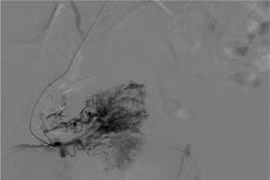

Nút mạch điều trị chảy máu tử cung do thông động tĩnh mạch hiếm gặp

Phụ nữ khi có triệu chứng ra máu âm đạo không đúng kỳ kinh, hay kéo dài bất thường, cần khám sớm để ngăn ngừa nguy cơ xuất huyết nặng, bảo vệ sức khỏe sinh sản.

Ra máu âm đạo ồ ạt do bất thường mạch máu tử cung hiếm gặp

Bất thường nối thông động tĩnh mạch trong cơ tử cung rất hiếm gặp, có thể gây ra tình trạng xuất huyết ồ ạt, kéo dài, đe dọa tính mạng người bệnh.

Bảo tồn tử cung cho người phụ nữ 35 tuổi bị bệnh lý mạch máu hiếm gặp

Bệnh viện Gia Đình (Đà Nẵng) vừa cứu sống nữ bệnh nhân 35 tuổi bị xuất huyết âm đạo nghiêm trọng do thông động tĩnh mạch tử cung - bệnh lý mạch máu hiếm gặp.